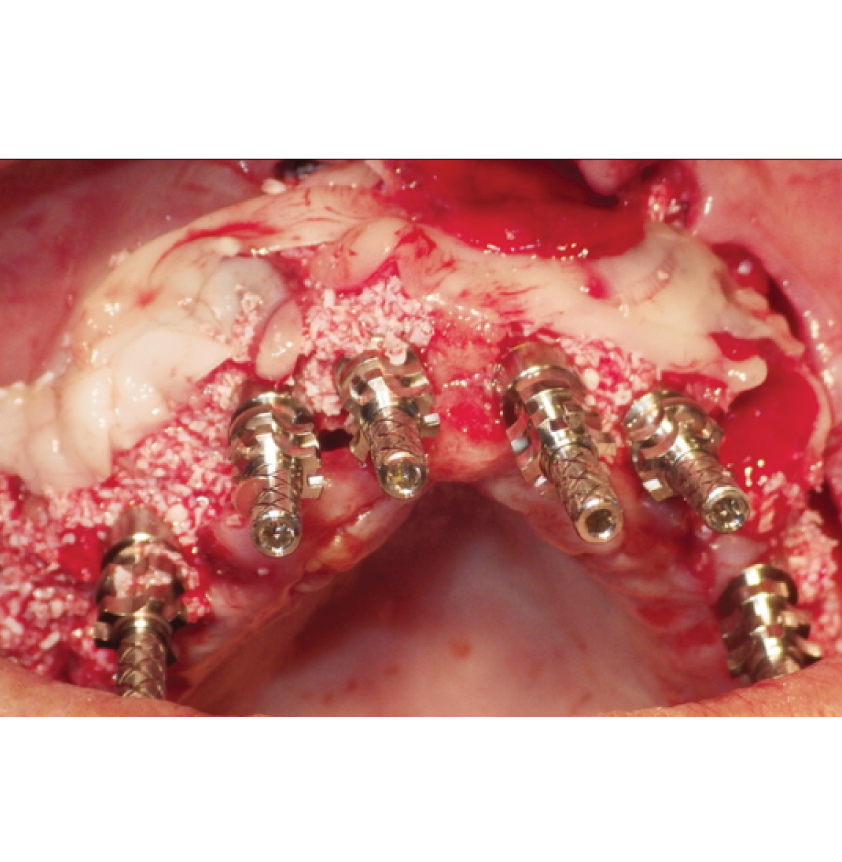

Director’s Clinical Cases

Director’s Clinical Cases